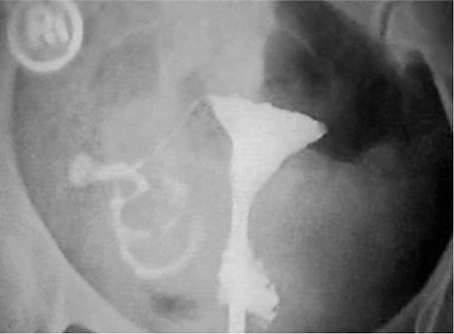

A Bilateral Cornual Block Before Treatment B Patent Bilateral